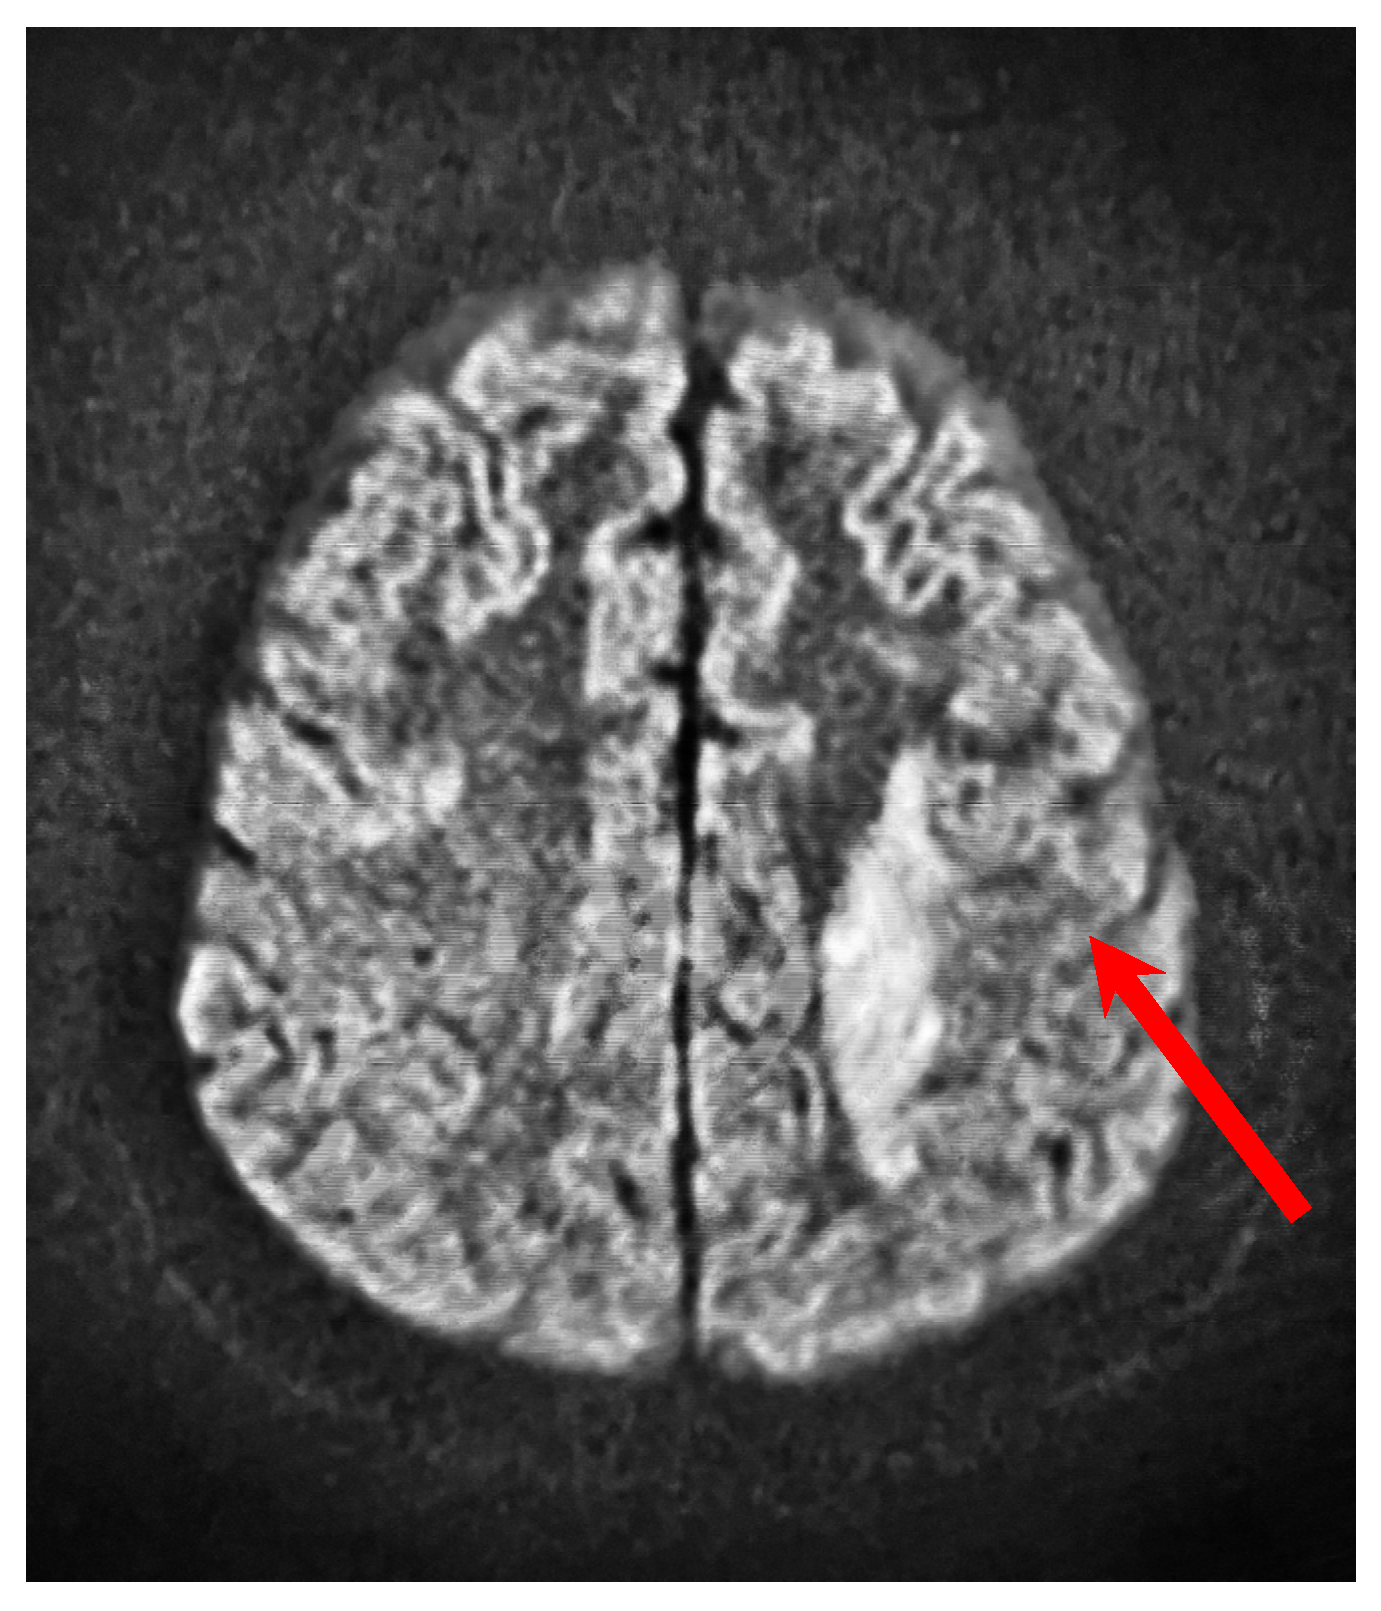

MRI of the head showed a focus of an ischemic stroke on the left side, with a diameter of 62 × 20 mm. Figure 3 shows the stroke focus in the MRI scan of the head.

Figure 3.

MRI scan of the head—baseline. The red arrow indicates the stroke focus.